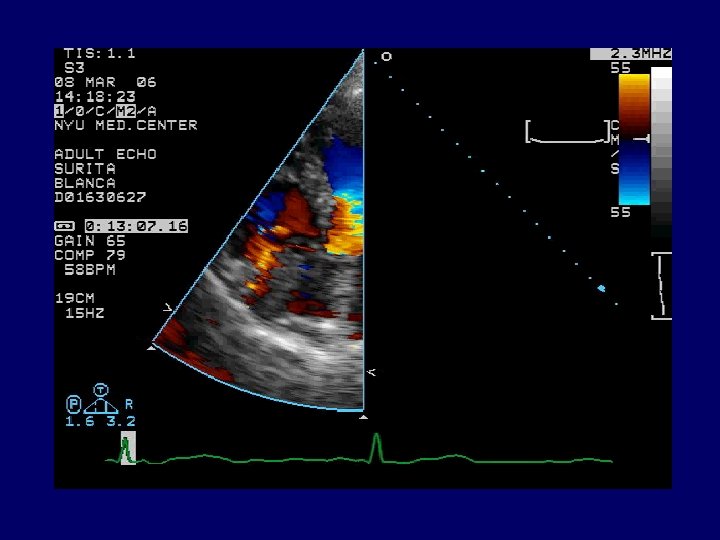

Radiology CXR: mild interstitial edema and cardiomegaly. Transthoracic echocardiogram (TTE): large 6. 5 x 2. 0 cm pedunculated mass attached to the lateral free wall of the right atrium separate from the tricuspid valve leaflets, with prolapse of the mass across the tricuspid valve and associated severe tricuspid insufficiency. A diagnostic procedure was performed…

Echocardiography

DDx : Intracardiac Mass 80% of myxomas are left sided Primary cardiac tumor Benign – 75% Malignant Either ! Secondary tumor Thrombus Vegetation

Evaluation of cardiac mass On cardiac MRI, avascular masses (thrombus) can be differentiated from tumors as they appear hypointense in T 2 weighted images and do not enhance with contrast. Differentiating between thrombus and vegetations from tumors using noninvasive means is crucial as it may determine the need for and timing of resection.